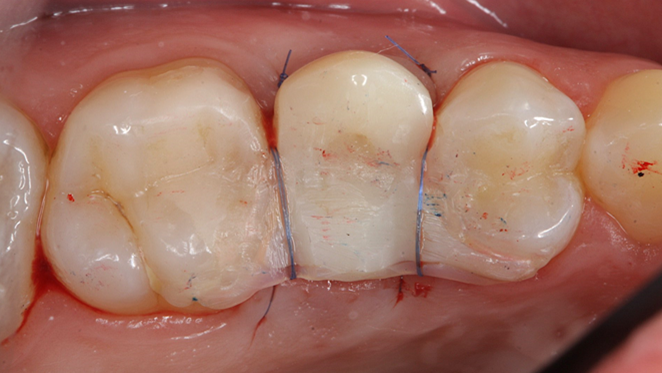

Clinical case: Extraction, immediate implant placement, & provisionalization

- Courtesy of Dr. Iulian Filipov, Romania -

Keywords

AnyRidge, R2GATE, guided surgery, immediate placement, immediate provisionalization, initial stability, Dr. Iulian Filipov, #25, maxillary posterior, immediate loading, Mega ISQ